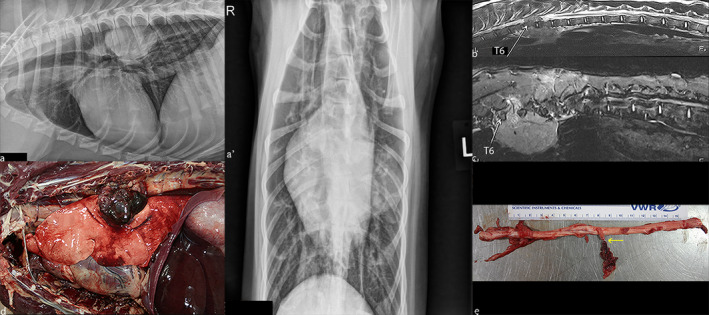

On thoracic radiographs, a well‐defined soft tissue mass (88 × 44 × 60 mm) was present within the left hemithorax extending from the fifth to the seventh intercostal spaces. On the lateral projections, the mass was in the dorsal third of the thorax, dorsal to the carina and ventral to the vertebral bodies of T6–T8. On the ventrodorsal projection, the mass was superimposed on the caudal subsegment of the left cranial lung lobe. There were no radiographically evident osseous changes, pulmonary metastasis or intrathoracic lymphadenomegaly. The remainder of the thoracic structures were also considered to be within normal limits (Figure 1a).

FIGURE 1.

Comparative appearance of the mass on radiographs (a), on MRI (b, c) and on post‐mortem examination (d, e). A, Right lateral (a) and ventrodorsal (a’) projection of the thorax showing a large well‐defined soft tissue mass within the left hemithorax. The mass is located within the dorsal third of the thorax, just above the carina and ventral to the vertebral bodies of T6–T8. There is no appreciable bony involvement. (b) Sagittal T2‐weighted image on midline. A heterogeneous extradural mass, hyperintense compared with the surrounding musculature is seen. The mass extended from the dorsal thoracic cavity towards the vertebral bodies of T6–T8. (c) Sagittal STIR image on the right of midline, there is at the level of T7–T8 invasion of the dorsal paraspinal musculature by some markedly hyperintense tissue extending from the spinal column. This was not appreciated on any of the previous sequences. On the right ventral side of the vertebral bodies of T6–T7, there is a 59 × 17 × 18 mm (length, width, height) mildly hyperintense well‐defined mass compared with the surrounding musculature. (d) Necropsy examination of the left thoracic cavity reveals an 80 × 70 × 40 mm multilobular mass exiting the left sixth and seventh intervertebral space that compresses the left caudal lung lobe. (e) Within the spinal canal, there is a 20 mm in diameter, lobulated, haemorrhagic and necrotic mass involving the left seventh thoracic spinal nerve roots and spinal nerve (arrow) apparently continuous with the thoracic mass outside the foramen (not depicted on the picture above)

On T2‐weighted images, there was a large extradural mass measuring 80 × 50 × 50 mm (length, width, height) extending from T6 to T8 (Figure 1b). At this level, it occupied between 66% and 75% of the lumen of the vertebral canal and was lateralized to the left side, thus causing severe spinal cord compression (Figure 2a). The mass was heterogeneously hyperintense compared with the surrounding musculature and extended through the left intervertebral foramina towards the dorsal aspect of the thoracic cavity where it was multilobulated. The left intervertebral foramen at T7–T8 appeared enlarged due to the presence of the expansile mass. The mass also extended along the right ventral side of the vertebral bodies of T6–T7 into the right dorsal thorax.

Transverse T2‐weighted pre‐ (a) and T1‐weighted pre‐contrast (b), T1‐weighted post‐contrast (c) administration at the level of T7, and T1 post‐contrast administration in the dorsal plane (d): The mass is heterogeneously hyperintense on the T2‐weighted pre‐contrast sequences with invasion of the spinal canal, surrounding musculature and dorsal aspect of the thoracic cavity on the right side (a). The mass was isointense to the musculature on the T1 pre‐contrast sequences (b). On the post‐contrast T1 images (c, d), there is heterogeneous contrast enhancement of the mass which is stronger dorsally. On the dorsal plane, the two aspects of the mass can be seen on both sides of the vertebrae

On gross examination, there was a large multilobulated mass in the dorsal aspect of the mid‐thoracic cavity with the following main areas.

In the left thoracic cavity, there was an 80 × 70 × 40 mm (length, width, height) multilobular mass that compressed the left caudal lung lobe (Figure 1d). This mass was tightly adhered to the parietal pleura, covering the ventral aspect of the seventh and eighth thoracic vertebrae and the aortic adventitia. The mass was mottled red to purple, multilobular, haemorrhagic and necrotic. Multifocally, the mass contained firm, tan to creamy‐white, approximately 5–15 mm in diameter nodules and infiltrated the seventh intervertebral space and foramen and the muscle surrounding the transverse processes of the seventh and eighth thoracic vertebrae.

In the right thoracic cavity, there was a 35 × 20 × 20 mm (length, width, height) multilobular mass, which was also tightly adhered to the ventral aspect of the sixth and seventh thoracic vertebrae.

Within the spinal canal, there was a 20 mm in diameter, lobulated, haemorrhagic and necrotic mass continuous with the thoracic mass outside the foramen noted above (Figure 1d). The mass involved the left seventh thoracic spinal nerve roots and spinal nerve abutting and mildly compressing the adjacent spinal cord at T7–T8 (Figure 1e). The mass was in very close contact but did not invade the adventitia of the descending aorta.